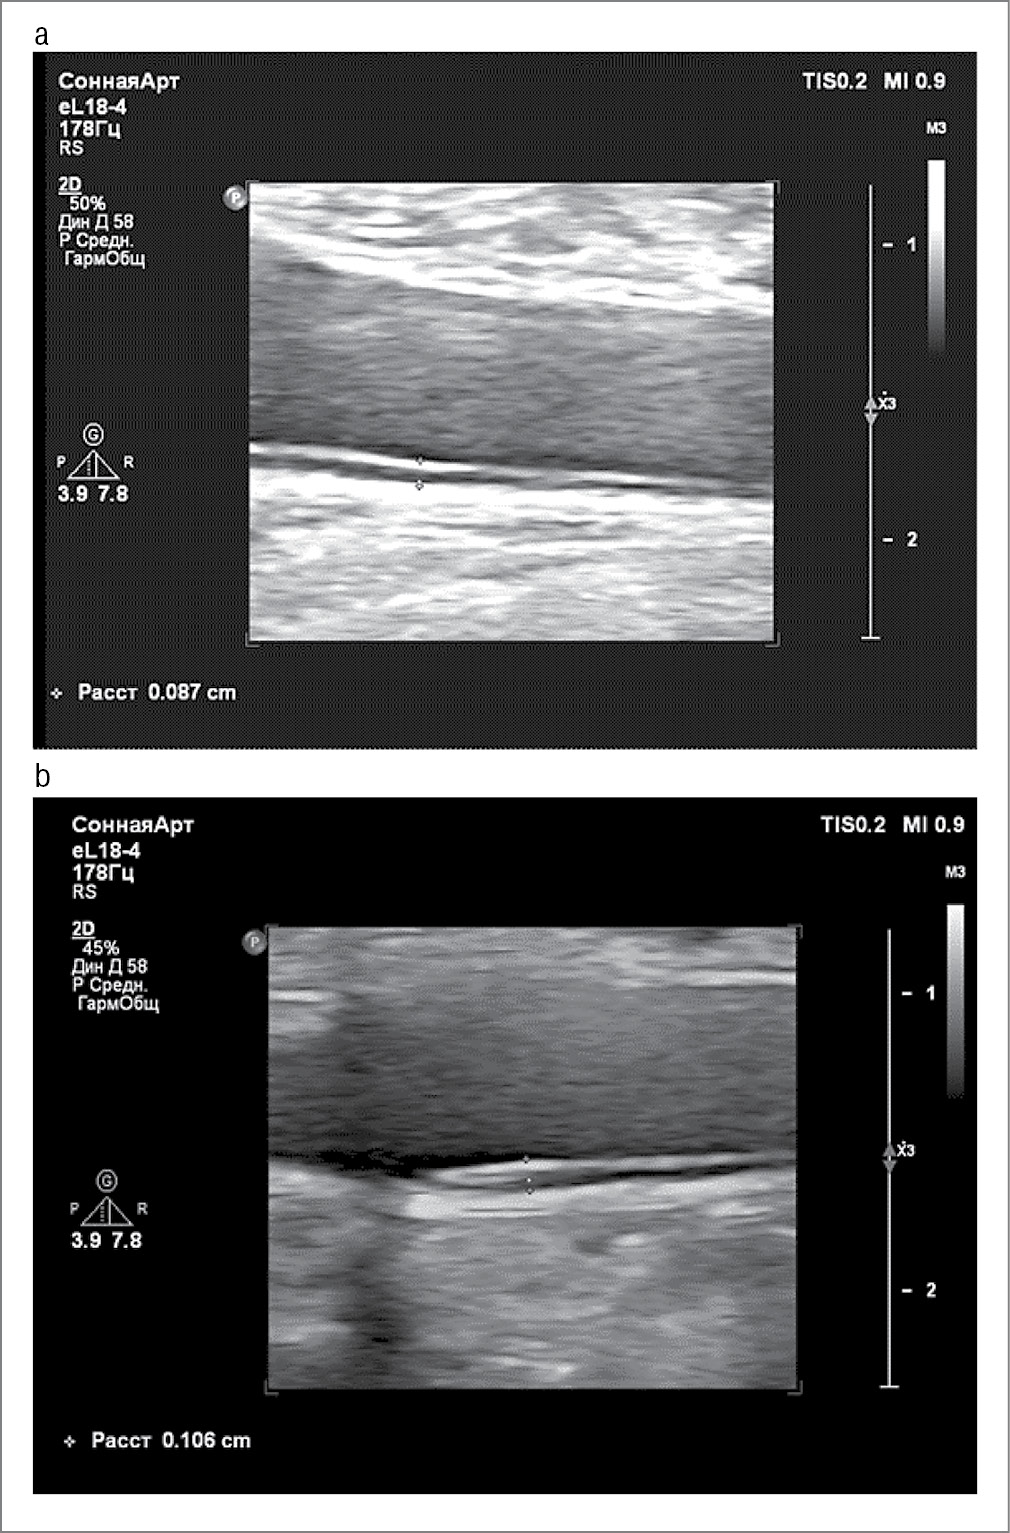

Средние значения структурных показателей стенки ОСА (толщины КИМ) исходно статистически значимо в группах не отличались (p>0,05). Сводные значения КИМ ОСА как раннего маркера атеросклероза и повышенного риска кардиоваскулярных событий приведены в табл. 2. Через 1 год наблюдения среднее значение КИМ ОСА в группе 1, где пациентки получали комплексную курсовую терапию с добавлением эндотелиотропного препарата, снизилось на 3,7%, а в группе 2 выросло на 26,8%.

Толщина КИМ>1 мм через 1 год наблюдения выявлена только в группе 2 (рис. 2). Здесь же отмечены более выраженные атеросклеротические изменения, в том числе появление атеросклеротических бляшек.

Рис. 2. Ультразвуковая оценка толщины КИМ ОСА у пациентки из группы 2: а – при включении в исследование (0,87 мм); b – через 1 год (1,06 мм).

Fig. 2. Ultrasound assessment of the IMT-CCA in a patient from group 2: a – at enrollment (0.87 mm); b – after 1 year (1.06 mm).